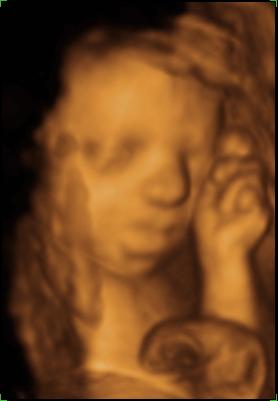

Bence 18 hetesen